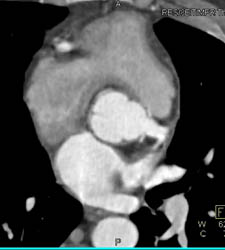

Repaired Aortic Root With Implanted Coronary Arteries